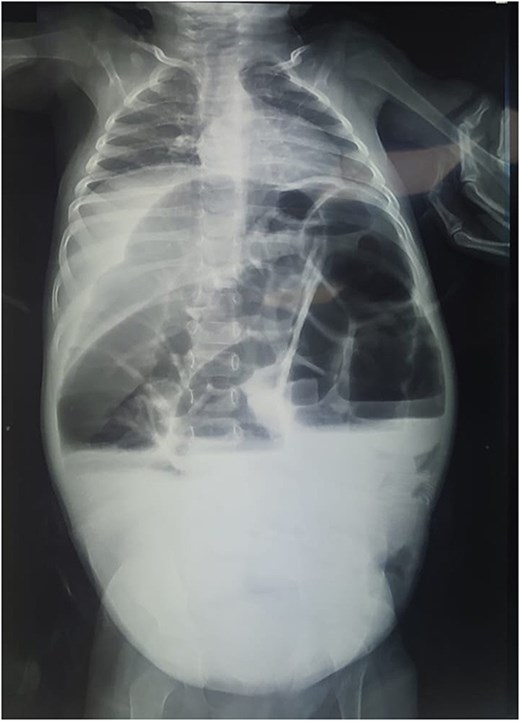

Reviewing the medical record of the patient, she underwent variable blood tests that were negative mostly except for ionogram disturbances due to malnutrition and dehydration. An abdominal X-ray was performed at each episode of hospitalization, that revealed intestinal-type hydroaeric levels and gastric stasis (Fig. 1) then a digestive fibroscopy with multiple biopsis as well as eosogastroduodenal transit were run out suggesting gastritis. A barium index (Fig. 2) was also performed on his last hospitalization suggesting a small bowel obstruction which also appeared on the Enteroscan (Fig. 3).

Enteroscan image showing an intestinal distension downstream of an obstacle.